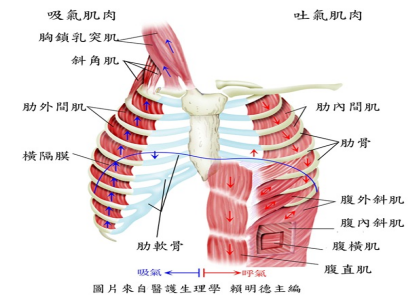

我们的呼吸(xī)运(yùn)动是由呼吸(xī)肌(jī)收缩舒张(zhāng)引(yǐn)起的胸廓扩大与(yǔ)缩小(xiǎo)的变化,当呼吸(xī)功能出现问题时,会(huì)使新鲜空气进入肺部的比重减(jiǎn)少,导致(zhì)身(shēn)体内器官的无法顺利运作与代谢,使得身体(tǐ)出现(xiàn)各种(zhǒng)问题。

呼吸(xī)肌(jī)训练是(shì)一种力(lì)量训练,其利用呼吸肌的可塑造(zào)性,通过在吸气或(huò)呼气过程中施加(jiā)阻(zǔ)力,呼吸肌(jī)克(kè)服阻力做功,以提高肌力达到肺康复目的。